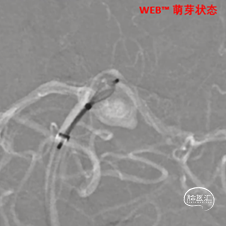

缓慢推出WEB™从种子至萌芽状态,继续向瘤腔内远端缓慢推送WEB™至萌芽至开花间状态;将WEB™和VIA™送至瘤顶,固定WEB™推送杆回撤VIA™,WEB™完全释放。